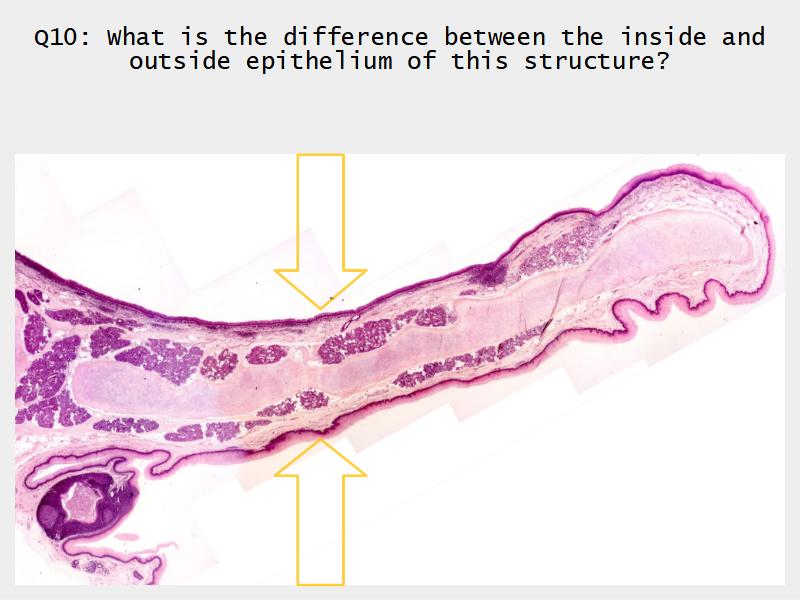

Epiglottis

Respiratory epithelium

- Pseudostratified

- Ciliated

- Columnar

- Epithelium with

- 4 Cells

- Ciliated columnar cells

- Non-ciliated columnar cells

- Goblet cells

- Basal cells